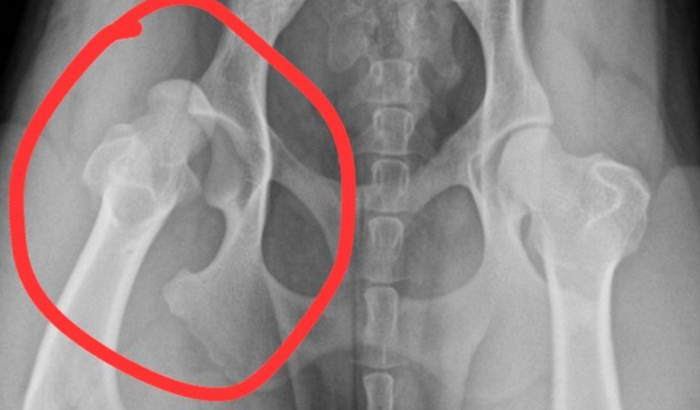

Levamos no veterinário fizemos o raio x e o laudo deu luxação, seu lado direito ta fora do lugar.

Para poder voltar a brincar como antes ela precisa passar por uma cirurgia.